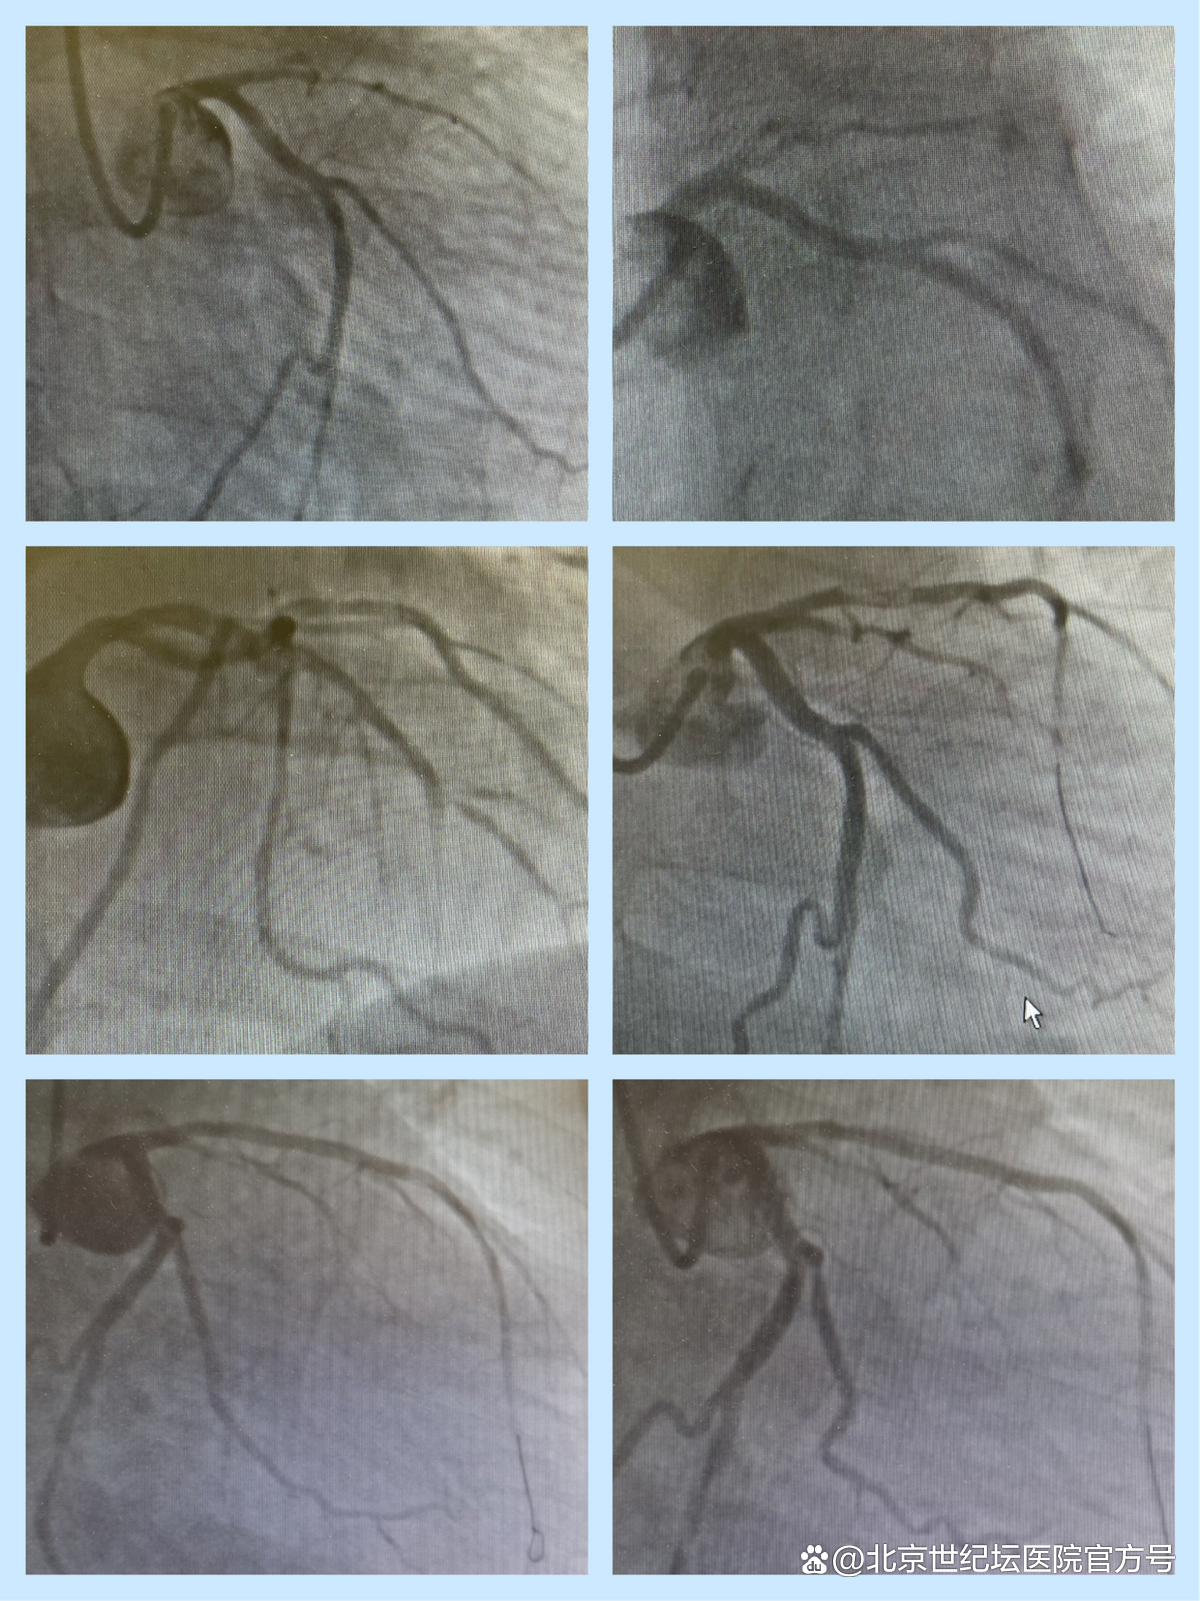

2月7日8:30,住院医师凡永艳和王子腾护送病情相对稳定的周先生进介入中心手术室。冠脉造影提示,本次心梗的罪犯血管为前降支,前降支近段完全闭塞。彭建军主任全程坐镇导管室指导手术,经验丰富的导管室护理组赵霞老师披挂上阵,协助陈策医生和赵博医生顺利完成冠脉介入手术。

冠脉影像资料